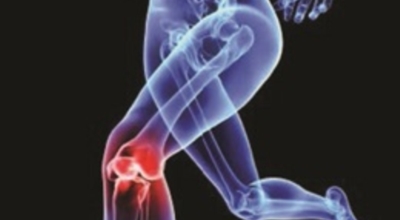

콘드로이친에는 관절 통증 감소 효험도 있어요. 콘드로이친은 보통 관절염으로 인한 무릎 통증을 관리하기 위해 사람들이 다량 필요로 하는 물질입니다. 관절염의 증상을 덜어줄 수는 있지만 섭취로 인한 효과가 영구적으로 지속되지는 않습니다. 그렇기 때문에 별개의 관절염 치료와 복용을 병행하시는 것이 더 좋습니다.

나이가 점점 들수록 보행 속도가 자연적으로 느려지게 되는데, 그 이유는 바로 관절의 노화 때문이죠. 노화가 진행되면 연골 손실이나 관절 간격이 짧아짐에 따라 관절염이 발생하고, 그로 인해 통증이 생겨 보행력이 점점 저하가 될 수 밖에 없다고 합니다. 그래서 나이가 들수록 콘드로이친을 보충시켜 주는 것이 보행능력 개선에 도움을 줄 수 있는 방법중 하나 입니다.

관절염으로 인한 통증은 환자의 몸의 기능을 쇠약하게 만들기도 합니다. 좀 더 디테일하게 말하자면, 관절염으로 말미암아 몸을 움직이지 않아 일상 활동과 삶의 질에 영향을 미치게 돼요. 한 프랑스에서 모두 만들어진 연구에 근거하면 12개월간 관절염 환자에게 하루에 800mg의 콘드로이친을 제공한 결과 위약을 복용시킨 대조군에 대조해 기능 역량이 50% 안과 밖으로 향상된 결과가 나왔습니다. 또 다른 연구를 보면 콘드로이친 복용이 무릎 관절의 마찰 계수를 감소시키는 것으로 보여 집니다. 즉, 연골이 보다 부드럽게 움직일 수 있도록 도와 관절 기능에 도움되는 것 이예요.

콘드로이친에는 염증을 억제하는 항염증 효과가 있어 관절염에 사용되는 물질인 만큼, 연골을 지켜주는 효험뿐 아니라 염증을 억제하는 역할이 매우 중요합니다. 콘드로이친에서는 염증을 억제하는 항염증 효과가 있다는 사실이 연구저널 Osteoarthritis Cartilage에서 규명된 바 있답니다. 이후 임상 및 실험의학 국제저널에서 콘드로이친 장기 섭취 시 손상된 연골이 정상 연골과 비슷하게 개선될 수 있다는 연구결과를 발표 하였습니다.